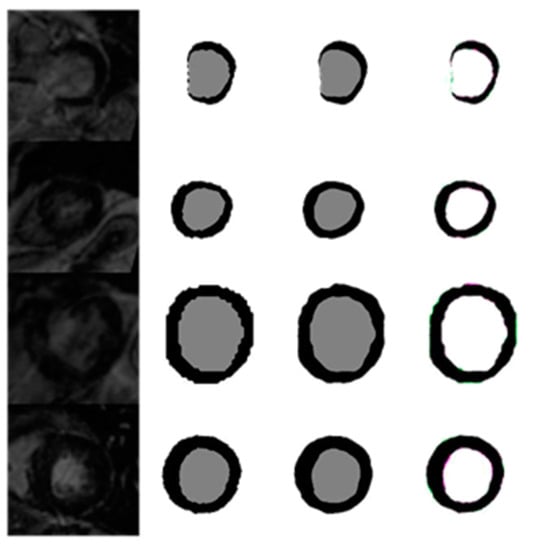

4.1.6. Evaluation of Automated Segmentation with U-Net and GT Segmentation Using LGE MRI Test Images